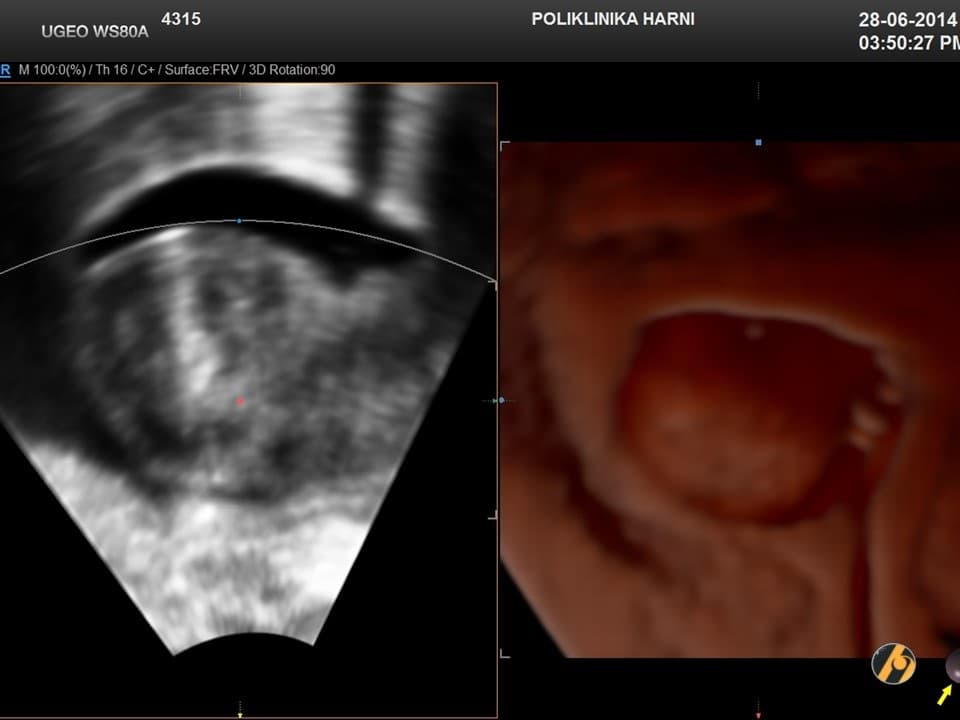

Dijagnoza

Dijagnoza mioma postavlja se temeljem anamnestičkih podataka, ginekološkog i ultrazvučnog pregleda. Ponekada su, osobito kod gigantskih mioma nužne dopunske metode kao što su intravenska urografija, CT ili MRI zdjelice, kako bi se u planiranju operativnog zahvata mogao procijeniti utjecaj mioma na okolne organe, a time i rizik povrede tih organa tijekom operacije.

Dijagnoza se postavlja ginekološkim pregledom i slikovnim pretragama.